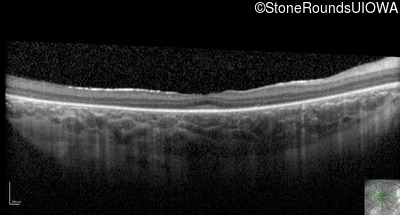

Optical Coherence Tomography - Right - Light Perception

Exemplar / OCT Stack

Optical Coherence Tomography - Left - Hand Motion 1'